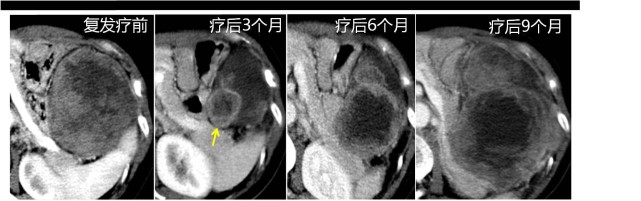

再回到老杨的故事。老杨经过治疗以后成功切除了肿瘤,也看到了他的小外孙。但是两年之后,他又回来了,发现肿瘤复发,腹腔里又新发了一个大肿块。

临床医生马上又给他用上了靶向药物,治疗了三个月之后,肿瘤整体明显缩小了,似乎效果很好,但是我们看到在它的后方又出现了一个新的活性结节,长得非常快。这也是现在一些新兴治疗如靶向及免疫治疗过程中可能会面对的问题,对一些肿瘤的疗效确实非常好,可以短期内使其迅速缩小,但是由于肿瘤异质性的原因,一部分耐药的组织又会迅速增大,短期内快速进展。这时候我们赶紧给他加量、换用二线药物,但是已经控制不住了。后期肿瘤占据了几乎大半个腹腔。后来老杨还是没能陪女儿继续走下去。

图片(老杨肿瘤复发与治疗的过程犹如“过山车”)

其间跟老杨聊过一次,他说晚上躺着睡觉的时候,能够听到“肿瘤生长的声音”。我到现在也没弄明白,肿瘤生长到底是什么声音,但确实有些肿瘤长得非常快,所以需要引起患者的警惕,积极通过影像手段评判后尽快治疗或调整方案。所以,现在的靶向治疗,在治疗初期可能是一个月或一个半月来复查。患者可能有疑问,为什么要给我做这么多的检查?术后也有患者会问,我都做完手术了,瘤子都切掉了,干嘛还检查?

而老杨的经历就能回答这样的问题。他的肿瘤复发,长到直径10厘米时才来复查。如果能在术后定期规范复查,在复发早期,肿瘤只有几厘米的时候就发现,从而尽快用药治疗,或者尽早地调整方案,有没有可能会获得更好的结果,这也是我们时常思考的。